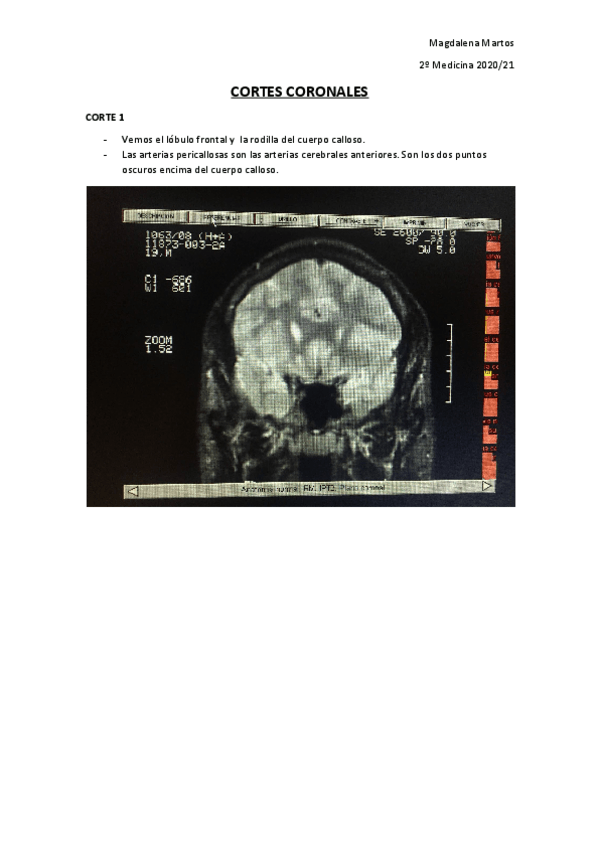

RESONANCIAS EXAMEN PRÁCTICO

He publicado nuevos apuntes de 2º Neurobiología: RESONANCIAS EXAMEN PRÁCTICO

Cortes-Coronales-Practico-Nuero.pdf